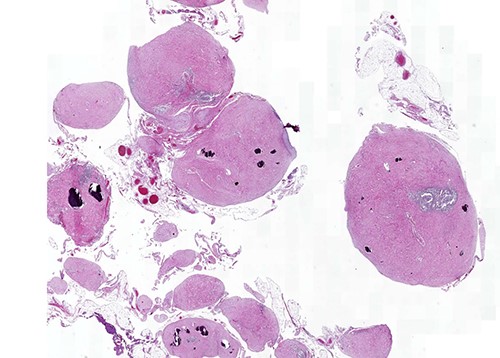

A 28-year-old male patient was admitted to the hospital with complaints of abdominal pain, prolonged swelling after meals, diarrhea of three to four times a day, black stools and weight loss of 3 kg in the last 2 weeks. His complaints started about 2 weeks after treatment for the COVID-19 infection. Diagnostic colonoscopy was performed and a biopsy was obtained from the terminal ileum. Biopsy results were evaluated together with the clinical findings, leading to the preliminary diagnosis of Crohn’s disease, and three doses of budesonide 3 mg/dose were started. The patient did not benefit from 1 month of treatment. Control physical examination, acute phase reactants, liver and kidney function tests were normal. Abdominal CT was performed with intravenous and oral contrast material (300/50 ml iohexol). Tomography revealed multiple scattered millimeter-sized nodular calcifications superficially located in the omentum in the right and left lower quadrants, clustered nodular calcifications of ~3.5 × 2 and 3 × 1 cm and omental heterogeneity. Abdominal viscera were normal (Supplementary Images 1 and 2). Laparoscopy was performed, with diffuse omental calcific nodules, partial adhesion of the omental fat tissue to the small intestine at the pelvic level, and a small amount of free serous fluid in the pelvis was detected (Fig. 1). The tumoral structures were removed by resection of two omental fragments of 15 ×5 × 2 and 8 × 7 × 1.5 cm.

On macroscopic examination, numerous (>100) gray-white-colored grape-like hard nodules were seen, with the largest measuring 4 cm and the smallest measuring 0.2 cm. They were well-circumscribed, unencapsulated, spherical or lobulated and cut surfaces were homogenous, gray-white and firm to rubbery. Microscopically, hypocellular spindle cell proliferations embedded in abundant hyalinized collagen were seen, occasionally dystrophic or psammomatous calcifications interspersed with sparse lymphoplasmacytic infiltrate that may form lymphoid follicles. There was no mitosis, atypia or necrosis (Figs 2 and 3).

Calcifying fibrous tumor with abundant paucicellular hyalinized collagen, interspersed psammomatous or dystrophic calcifications and inflammatory infiltrate consisting of lymphocytes and plasmocytes (H&E, ×4).